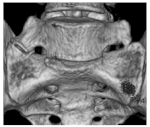

| I | Ia: Unilateral dysplastic transversal process > 19 mm Ib: Bilateral dysplastic transversal process > 19 mm | Ib![]() |

| II | IIa: Unilateral pseudarthrosis between transversal process and sacral bone IIb: Bilateral pseudarthrosis between transversal process and sacral bone | IIa![]() |

| III | IIIa: Unilateral bony union between transversal process and sacral bone IIIb: Bilateral bony union between transversal process and sacral bone | IIIb![]() |

| IV | Unilateral bony union contralateral pseudarthrosis between transversal process and sacral bone | IV![]() |